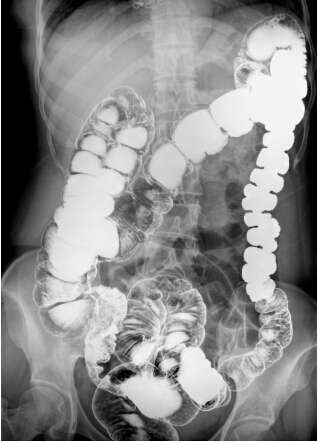

目前主流的DR成像面積都是17英寸×17英寸方形成像,這在臨床應(yīng)用中有巨大的優(yōu)勢(shì)。動(dòng)態(tài)DR在常規(guī)DR的基礎(chǔ)上實(shí)現(xiàn)新的技術(shù)突破,尤其是在成像尺寸上也是有了新的突破,也能實(shí)現(xiàn)17英寸×17英寸方形動(dòng)態(tài)影像的輸出。可以說(shuō)這是一個(gè)革命性的突破。比如:以前做一個(gè)全消化道造影,需要調(diào)整球管跟隨著造影劑的流向進(jìn)行實(shí)時(shí)觀察,往往只能觀察到局部的情況。一個(gè)正常體型的成年人做一個(gè)全消化道造影至少需要點(diǎn)三到四張片子才能看全,并且非常麻煩。

現(xiàn)在的動(dòng)態(tài)DR,成像視野非常大,一改過(guò)去圓形成像傳統(tǒng),的確大大有益于臨床醫(yī)生的便捷操作。一個(gè)幅面就能夠把一個(gè)正常的成年人的全消化道看全,并且影像非常的清晰,可以大幅減少觀察時(shí)間,減少病人吃線量。